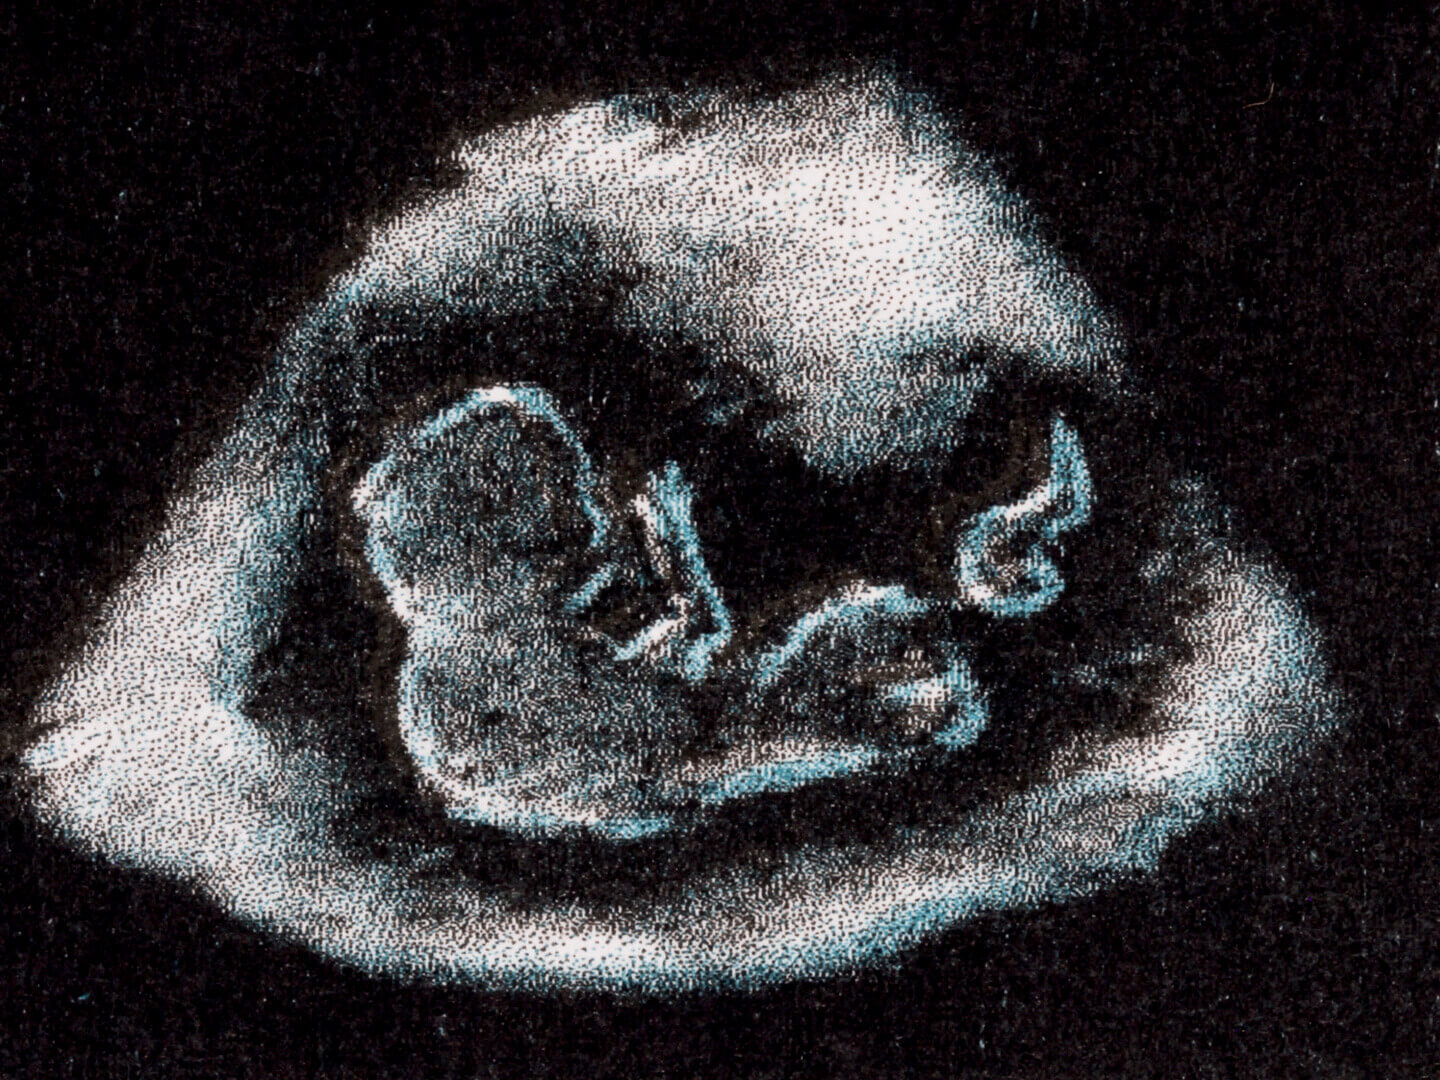

An experimental documentary that reveals both the facts and fantasies of the history of pregnancy tests from the 1930s-60s which relied on the use of live frogs and rabbits. These pregnancy tests changed the world: they expanded our understanding of hormones, gave women more reproductive choice, and caused ecological crisis- decimating certain amphibian populations.